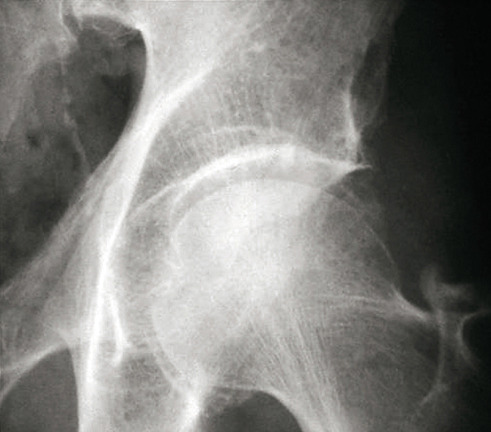

La forme pseudorhumatoïde est rare (5 %), simulant une polyarthrite rhumatoïde (diagnostic différentiel), avec parfois des signes systémiques d’inflammation (élévation de la vitesse de sédimentation et de la CRP). Le diagnostic repose sur la mise en évidence des cristaux de PPC. La radio peut mettre en évidence des calcifications des cartilages articulaires (fig. 6) et des fibrocartilages (fig. 7, 8, 9 et 10). L’échographie (plus sensible) peut mettre en évidence des dépôts de PPC, qui apparaissent comme une fine bande hyperéchogène au sein des cartilages hyalins et comme des points scintillants dans les fibrocartilages ou dans la membrane synoviale. Dans l’arthrite chronique à PPC, lespossibilités thérapeutiques sont, par ordre de préférence : colchicine (de 0,5 à 1 mg/j), petites doses de cortisone, parfois les AINS per os (mais leur prescription est souvent limitée par les comorbidités chez les patients âgés), méthotrexate et l’hydroxychloroquine. Il n’y a pas aujourd’hui de traitement « de fond », mais des molécules sont à l’étude.

L’arthrose associée aux dépôts de PPC touche en particulier les genoux, avec une symptomatologie chronique et/ou des accès aigus cristallins. Par comparaison avec l’arthrose idiopathique, elle serait à l’origine d’une symptomatologie plus inflammatoire, toucherait des articulations inhabituelles (radiocarpienne, carpienne, gléno-humérale, médio-pied et arrière-pied, cheville) et serait associée à plus d’ostéophytes et de géodes. Cette arthropathie dégénérative peut s’accompagner de lésions structurales sévères avec disparition rapide de l’interligne (arthropathies destructrices : hanches, genoux, poignets, coudes). Les objectifs et les modalités thérapeutiques sont identiques à ceux d’une arthrose idiopathique. Aucun traitement ne permet la dissolution des cristaux de PPC.